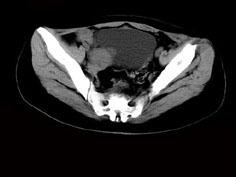

问题 女,24岁,近月余感尿频明显,CT检查如图,最可能诊断为 ( )

选项 A、盆腔纤维瘤 B、卵巢囊肿 C、子宫肌瘤 D、卵巢癌 E、膀胱癌

答案 A